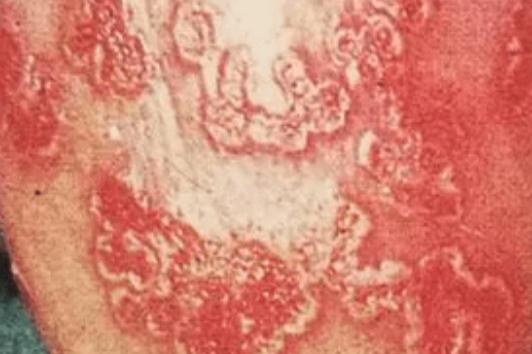

4、环状溃疡性龟头炎。这种类型的龟头炎在龟头和包皮上有红斑,逐渐扩大形成浅表溃疡。

2、滴虫性龟头炎:分泌物中可见滴虫。患处有红斑、丘疹,逐渐扩大,表面有水疱,然后糜烂、渗出。3、念珠菌性龟头炎:分泌物直接镜检念珠菌孢子和菌丝。早期潮红,针尖表面散在红色丘疹,覆盖有点奶酪样分泌物,脓疱,严重糜烂渗出。患者往往长期使用广谱抗生素或皮质类固醇,或患有糖尿病。